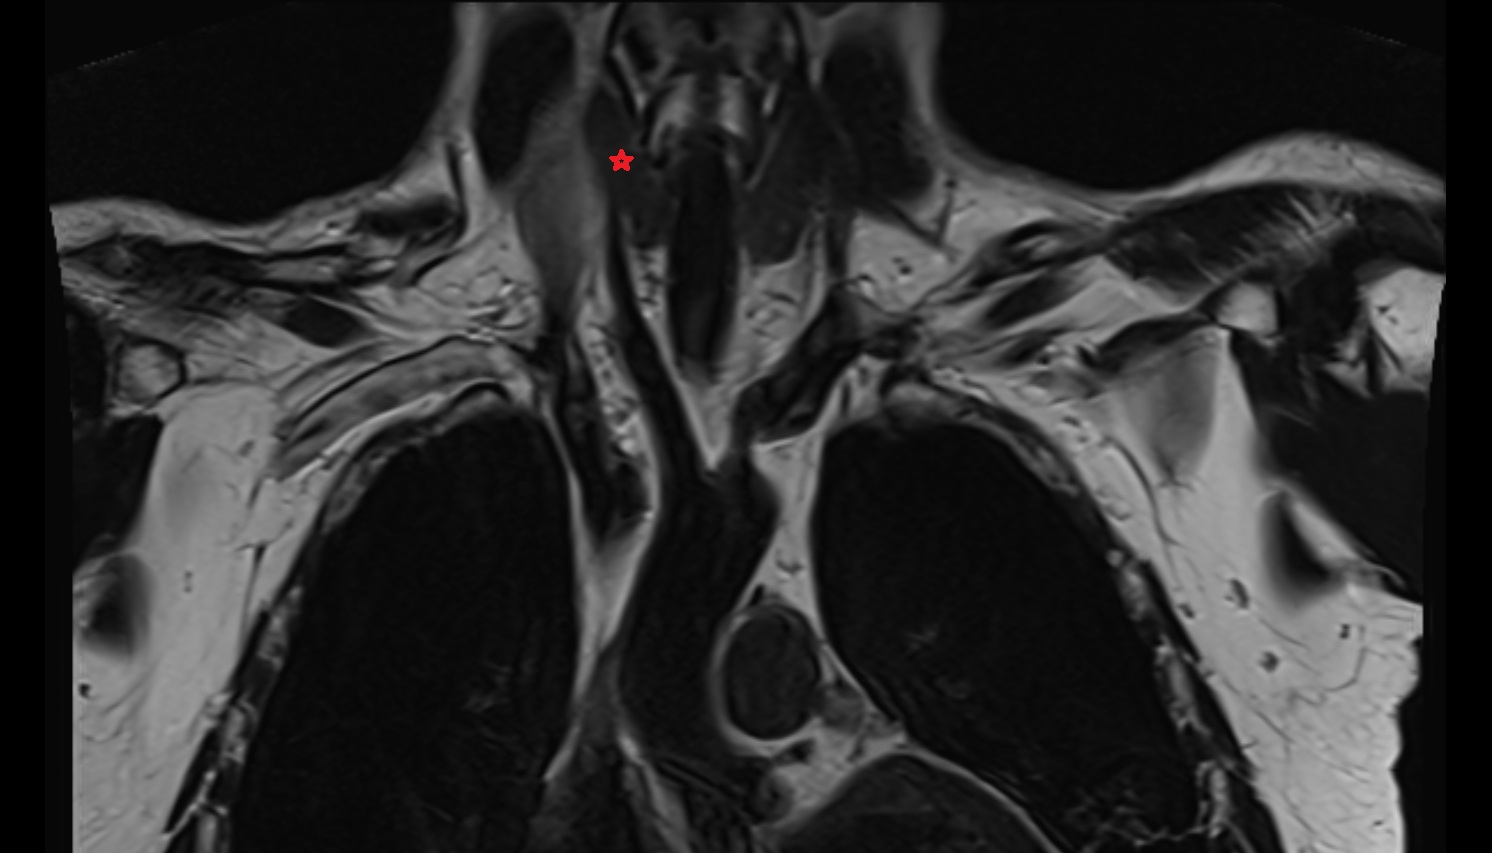

- Pituitary stalk

- Pituitary gland

- Optic chiasm